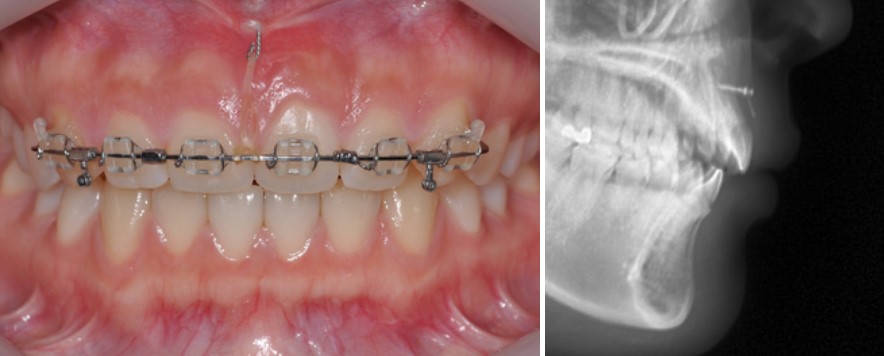

치료 계획: 옥니 각도 교정 + 후방 이동으로 거미스마일 완화

위 앞니를 옆에서 보면 치아 머리보다 뿌리 부분이 더 앞으로 나와 보이는 경우가 있는데,

이를 흔히 **‘옥니’**라고 부르기도 합니다.

이 옥니 형태의 앞니 각도를 정상 범위로 회복시키는 방법 중 하나가,

위 앞니 사이에 교정용 미니스크류를 식립해 위쪽 방향으로 끌어올리는 것(상방 견인) 입니다.

우선 위 앞니 6개에만 교정 장치를 부착하고, 미니스크류를 이용해 치아 각도를 바로잡는 치료를 먼저 진행했습니다.

약 4개월 정도가 지나자, 위 앞니 각도가 보다 정상적인 방향으로 회복되면서 웃을 때 보이는 잇몸량도 점차 줄어들기 시작했습니다.

다만 치아는 보통 뿌리 끝을 중심으로 회전하기 때문에, 예상대로 위앞니가 위로 올라가면서 아래 앞니와의 간격이 벌어지는 현상이 나타났습니다.

이제는 윗니를 뒤로 보내 아래 치아와 교합을 다시 맞추는 단계가 필요해졌습니다.

예쁜 스마일라인을 위해서는 어금니 부분의 상방 이동(위로 끌어올리기)도 함께 고려해야 했습니다.

환자분은 심미적인 이유로 위쪽은 설측교정(안쪽 장치) 을 원하셨기 때문에, 초기 바깥쪽 장치를 제거한 뒤 위쪽에는 설측 장치를 부착하고,

아래 치아에는 윗니와의 교합을 맞추기 위해 일반 교정 장치를 부착했습니다.

효율적인 후방 이동을 위해 치료 중 후반부에는 어금니 부위에 바깥쪽 교정장치를 추가하여 힘을 보다 효과적으로 전달했습니다.